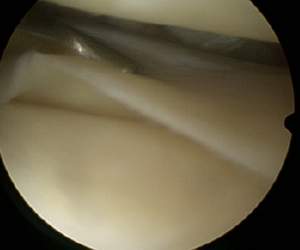

Arthroskopische Ansicht eines Meniskusrisses. Der Tasthaken ist der verlängerte Finger des Orthopäden und stellt den Riss dar.*